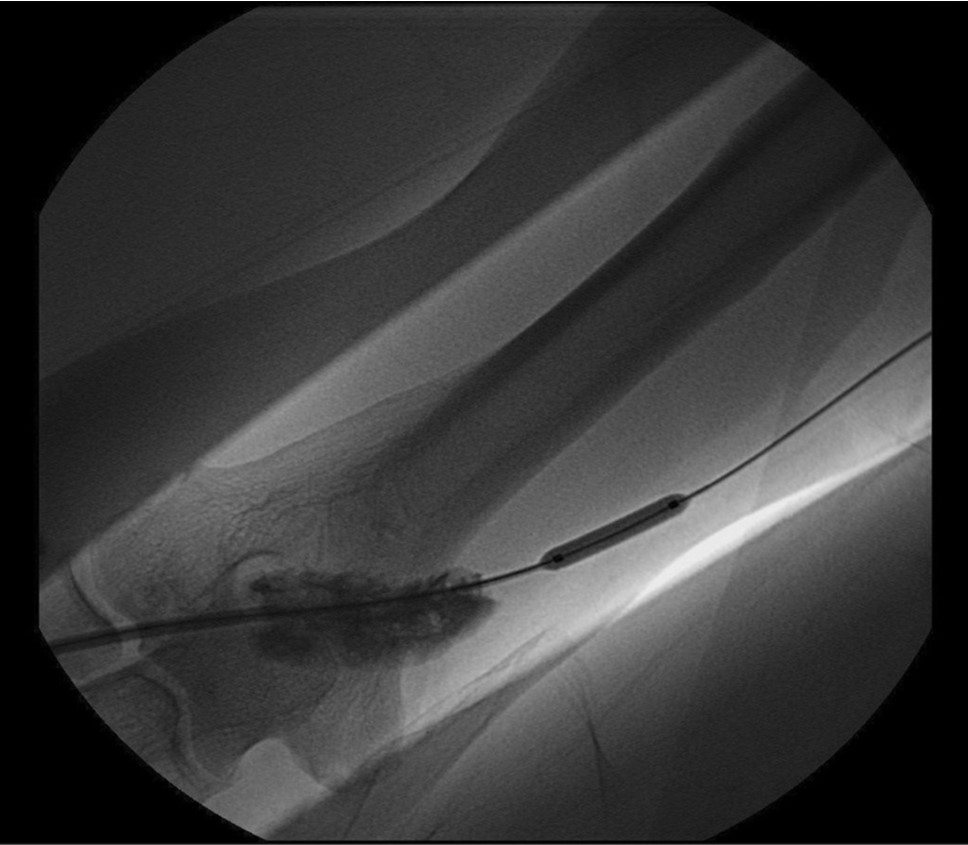

Initial shuntogram 상 total stenotic occlusion된 antecubital vein과 cephalic & basilic veins이 확인되었다(Fig. 1) 투시하에서 더 이상의 outflow vein을 확인할 수 없었으며 초음파상 1mm 크기에 가까운 흔적으로 확인되었다(Fig. 2). 7Fr, 24cm sheath(Accu-Sheath, Sung wonmedical, Korea, Cheongju) 로 폐색된 앞부위까지 전진시킨 후, 투시를 보조수단으로 하며 초음파를 main 유도 기구로 사용하여 real time으로 초음파 probe를 0.035’ J-tip & straight-tip guide wires(Terumo, Tokyo, Japan)와 5 Fr Kumpe catheter(Soft-Vu, AngioDynamics, USA, NY) 바로 위에 위치 시키면서 wire를 전진시켰다(Fig. 3). 시술 중 guide wire 가 혈관 외부로 뚫고 나가며 parenchymal injury를 유발하였다(Fig. 4A, B). 그 후 venous true lumen을 찾 angioplasty를 시행하였다(Fig. 5). 마지막 shuntogram 상 더 이상의 혈관 손상이 없이 재개통된 것을 확인하고 시술을 종료하였다(Fig. 6).

Fig. 4.

A-B. parenchymal rupture due to guide wire

Fig. 5.

Guide wire negotiation to true venous lumen and balloon angioplasty at antecuvital and basilica vein